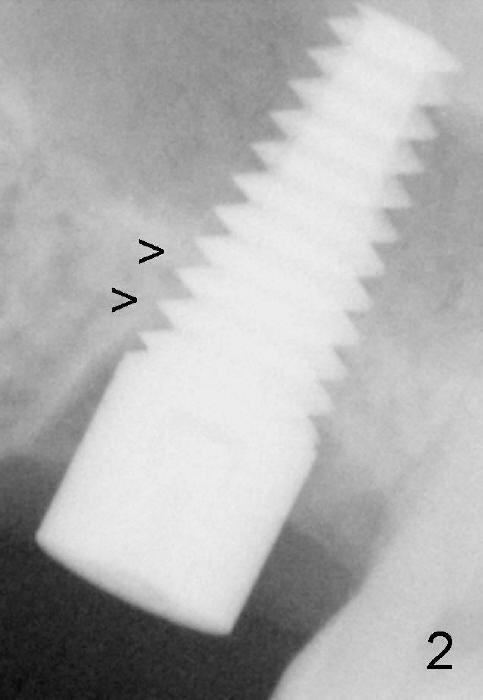

Prior to placement of 6x17 mm soft tissue level implant (Fig.1), the same size of tap is used. When the latter is removed, there is a small defect in the buccal wall of the osteotomy (mainly in the palatal socket) with the intact sinus membrane. There is no intraop or postop nasal hemorrhage. The patient returns for restoration 7 months postop; it appears that there is osteo-integration (Fig.2 with the mesial gap getting smaller (>)). The gingiva is healthy buccal (Fig.3: B) and palatal (Fig.4: P). The mesial gap is closed with formation of dense bone 4 years post cementation (Fig.7). Fig.5 is the preop PA of the patient, which shows that the palatal root (pink dashed line) is above the sinus floor and surrounded by the lamina dura. Fig.6 is a coronal section of the 2nd molar of another patient, which shows that the palatal root is 5-6 mm above the sinus floor. Upper Molar Immediate Implant Follow-Up Xin Wei, DDS, PhD, MS 1st edition 10/13/2013, last revision 05/18/2018